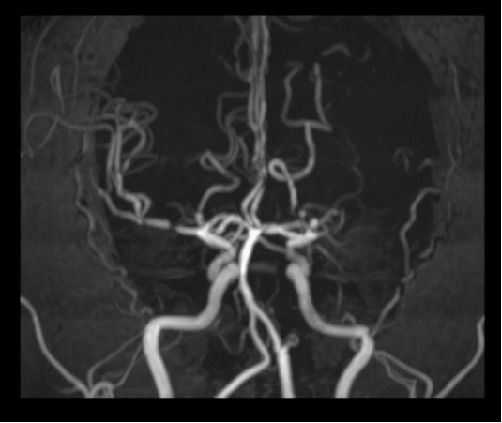

案例圖

顱腦MRA